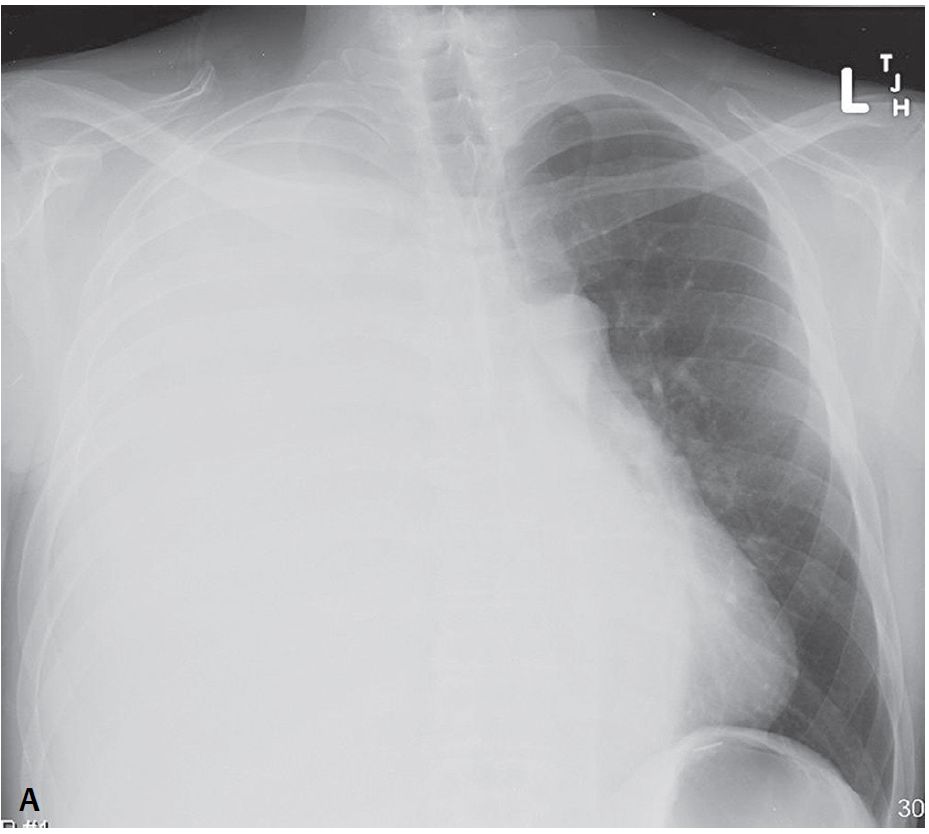

PA chest radiograph show complete “white-out” of the right hemithorax. No air bronchograms are seen and only the left diaphragm is perceptible on the lateral exam. Note the contralateral displacement of the tracheal air column and mediastinum “away” from the white-out on the PA exam.

Massive Unilateral Pleural Effusion; Hepatic Hydrothorax